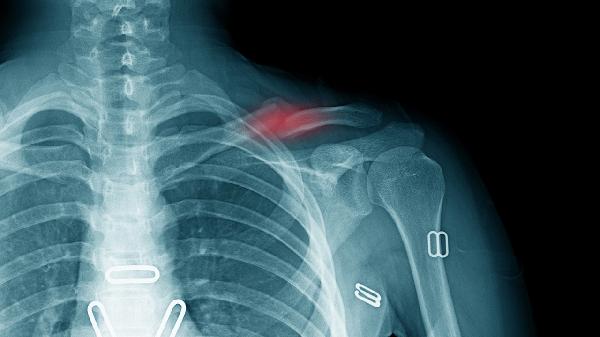

锁骨骨折保守治疗骨不连的可能性与骨折类型、固定方式及个体差异有关,通常可通过规范固定、营养支持、功能锻炼等方式降低风险。骨不连可能与固定不稳定、血供不足、感染等因素有关,通常表现为局部持续性疼痛、异常活动等症状。

保守治疗采用“8”字绷带或锁骨带固定时,若复位不良或固定松动易导致骨折端微动。长期异常应力刺激可能延迟愈合,需定期复查调整松紧度,避免过早负重。

锁骨中段骨折易损伤滋养血管,保守治疗无法直接修复血运。骨折端缺血可能形成纤维性连接而非骨性愈合,建议补充蛋白质、维生素D及钙质促进血管再生。

保守治疗期间每日摄入牛奶300ml、鸡蛋1-2个及绿叶蔬菜200g保障钙磷供给,6周内避免提拉重物。愈合期每周进行3次肩部等长收缩训练,若12周后仍无骨痂形成需考虑手术干预。术后康复阶段可尝试游泳、弹力带训练恢复关节活动度,定期拍摄X线片评估愈合进度。